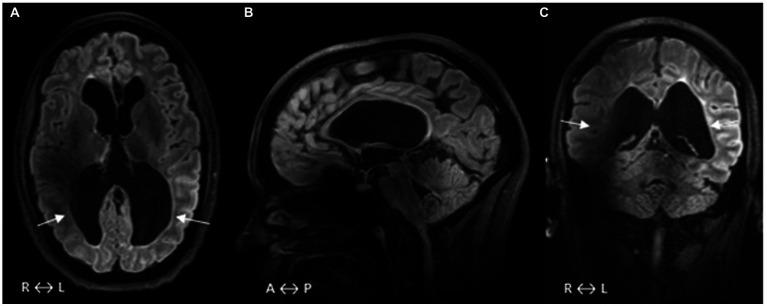

We describe the case of a 30-year-old woman, who needed a formal report on her visual impairment to seek support from society. She was born preterm, and during her neonatal period, she suffered from bilateral intraventricular hemorrhage (IVH) grade 3, a condition that can cause cerebral visual impairment (CVI) due to damage to the retro-geniculate visual pathways. Individuals with such brain damage of this severity are often restricted by cerebral palsy (CP) and intellectual disability, and thus have a limited ability to cooperate in the assessment of visual function. However, our patient was capable of providing reliable test results, and she manifested only a small island of central vision in each eye, with additional reduced visual acuities. She cooperated well in examinations involving MRI of the brain, optical coherence tomography (OCT) of retinal ganglion cells, and multi-focal visual evoked potentials, with each test providing information about potential limitations in the structural prerequisites for visual function. What distinguishes our case is the severity of the damage to the optic radiations and the massive secondary loss of most of her retinal ganglion cells (GCs). However, there is some measurable visual function, which may be due to developmental neuroplasticity during early development, when surviving GCs prioritize the central visual field. Despite her visual difficulties, she is a keen portrait painter. Our patient may be representative of, and a spokesperson for, other individuals with extensive brain damage of the same etiology, who are unable to perform perimetric tests and therefore run the risk of not being recognized as severely visually impaired, and consequently, not being given the best conditions for habilitation. OCT may serve as a helpful diagnostic tool. Aim: This study aims to describe visual behavior and practical applications of visual function in relation to structural prerequisites for visual function.

我们描述了一名30岁女性的病例,她需要一份关于其视力障碍的正式报告以寻求社会支持。她早产,在新生儿期双侧发生3级脑室内出血(IVH),这种情况可因膝状体后视觉通路受损而导致脑性视力障碍(CVI)。如此严重脑损伤的个体常受脑瘫(CP)和智力残疾的限制,因此在视力功能评估中合作能力有限。然而,我们的患者能够提供可靠的检测结果,她每只眼睛仅表现出一小片中心视力岛,且视力进一步下降。她在涉及脑部MRI、视网膜神经节细胞光学相干断层扫描(OCT)和多焦点视觉诱发电位的检查中配合良好,每项检查都提供了有关视力功能结构前提潜在局限性的信息。我们病例的独特之处在于视辐射损伤的严重程度以及她大部分视网膜神经节细胞(GCs)的大量继发性丧失。然而,仍存在一些可测量的视力功能,这可能归因于早期发育过程中的发育神经可塑性,此时存活的GCs优先考虑中心视野。尽管有视力困难,她仍是一位敏锐的肖像画家。我们的患者可能代表了其他病因相同、脑损伤广泛的个体,并成为他们的代言人,这些人无法进行视野检查,因此有不被认定为严重视力障碍的风险,进而无法获得最佳的 habilitation条件。OCT可能是一种有用的诊断工具。目的:本研究旨在描述视觉行为以及视觉功能在与视觉功能结构前提相关方面的实际应用。